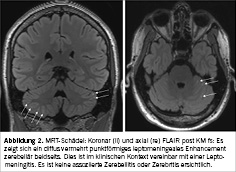

Sowohl eine Computertomografie (CT) des Neurocraniums als auch die ergänzende CT-Angiographie waren ohne pathologische Befunde. Nach wiederholt frustraner Lumbalpunktion erfolgte bei dringendem Verdacht auf eine infektiöse ZNS-Erkrankung eine empirische Therapie mit Ceftriaxon, Dexamethason sowie Aciclovir. MR-tomografisch zeigte sich sodann ein diskret vermehrtes Enhancement zerebellär beidseits, passend zu einer Leptomeningitis (Abbildung 2).